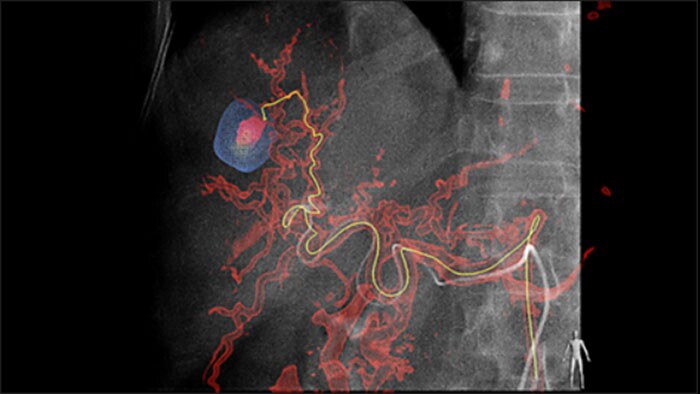

Automatic Feeder Detection kan de detectie van aanvoerende slagaders aanzienlijk verbeteren. EmboGuide ondersteunt u bij het maximaliseren van de effectiviteit van uw TACE-procedures, omdat het mogelijk uw gevoeligheid kan vergroten, het aantal fout-positieve resultaten kan verminderen en de overeenkomst tussen lezers kan maximaliseren1. EmboGuide biedt ook efficiënte, workflowgebaseerde live 3D-geleiding met automatische detectie van aanvoerende slagaders1.

Door het gebruik van chemo-/radioembolisatietechnieken zoals TACE en SIRT neemt de behoefte aan standaardisatie en efficiëntie toe. U moet de tumor(en) steeds opnieuw betrouwbaar en consistent lokaliseren, alle aanvoerende bloedvaten identificeren en de juiste interventionele aanpak plannen/uitvoeren. Onze Automatic Feeder Detection-oplossing kan de detectie van aanvoerende slagaders aanzienlijk verbeteren in vergelijking met het gebruik van alleen Cone Beam CT. EmboGuide ondersteunt u bij het maximaliseren van de effectiviteit van uw TACE-procedures, omdat het mogelijk uw gevoeligheid kan vergroten, het aantal fout-positieve resultaten kan verminderen en de overeenstemming tussen lezers kan maximaliseren.1

Het vermogen om levernodules te detecteren en te differentiëren en kleine aanvoerende vaten te identificeren is cruciaal voor het kiezen van de juiste therapie. Navigeren naar het interessegebied door alle aanvoerende vaten te bereiken, met behoud van selectiviteit voor de laesie, vergroot de kans op slaging. Bevestiging van het eindpunt van de behandeling en slaging van de behandeling terwijl de patiënt nog op tafel ligt, verhoogt het vertrouwen in de klinische resultaten.